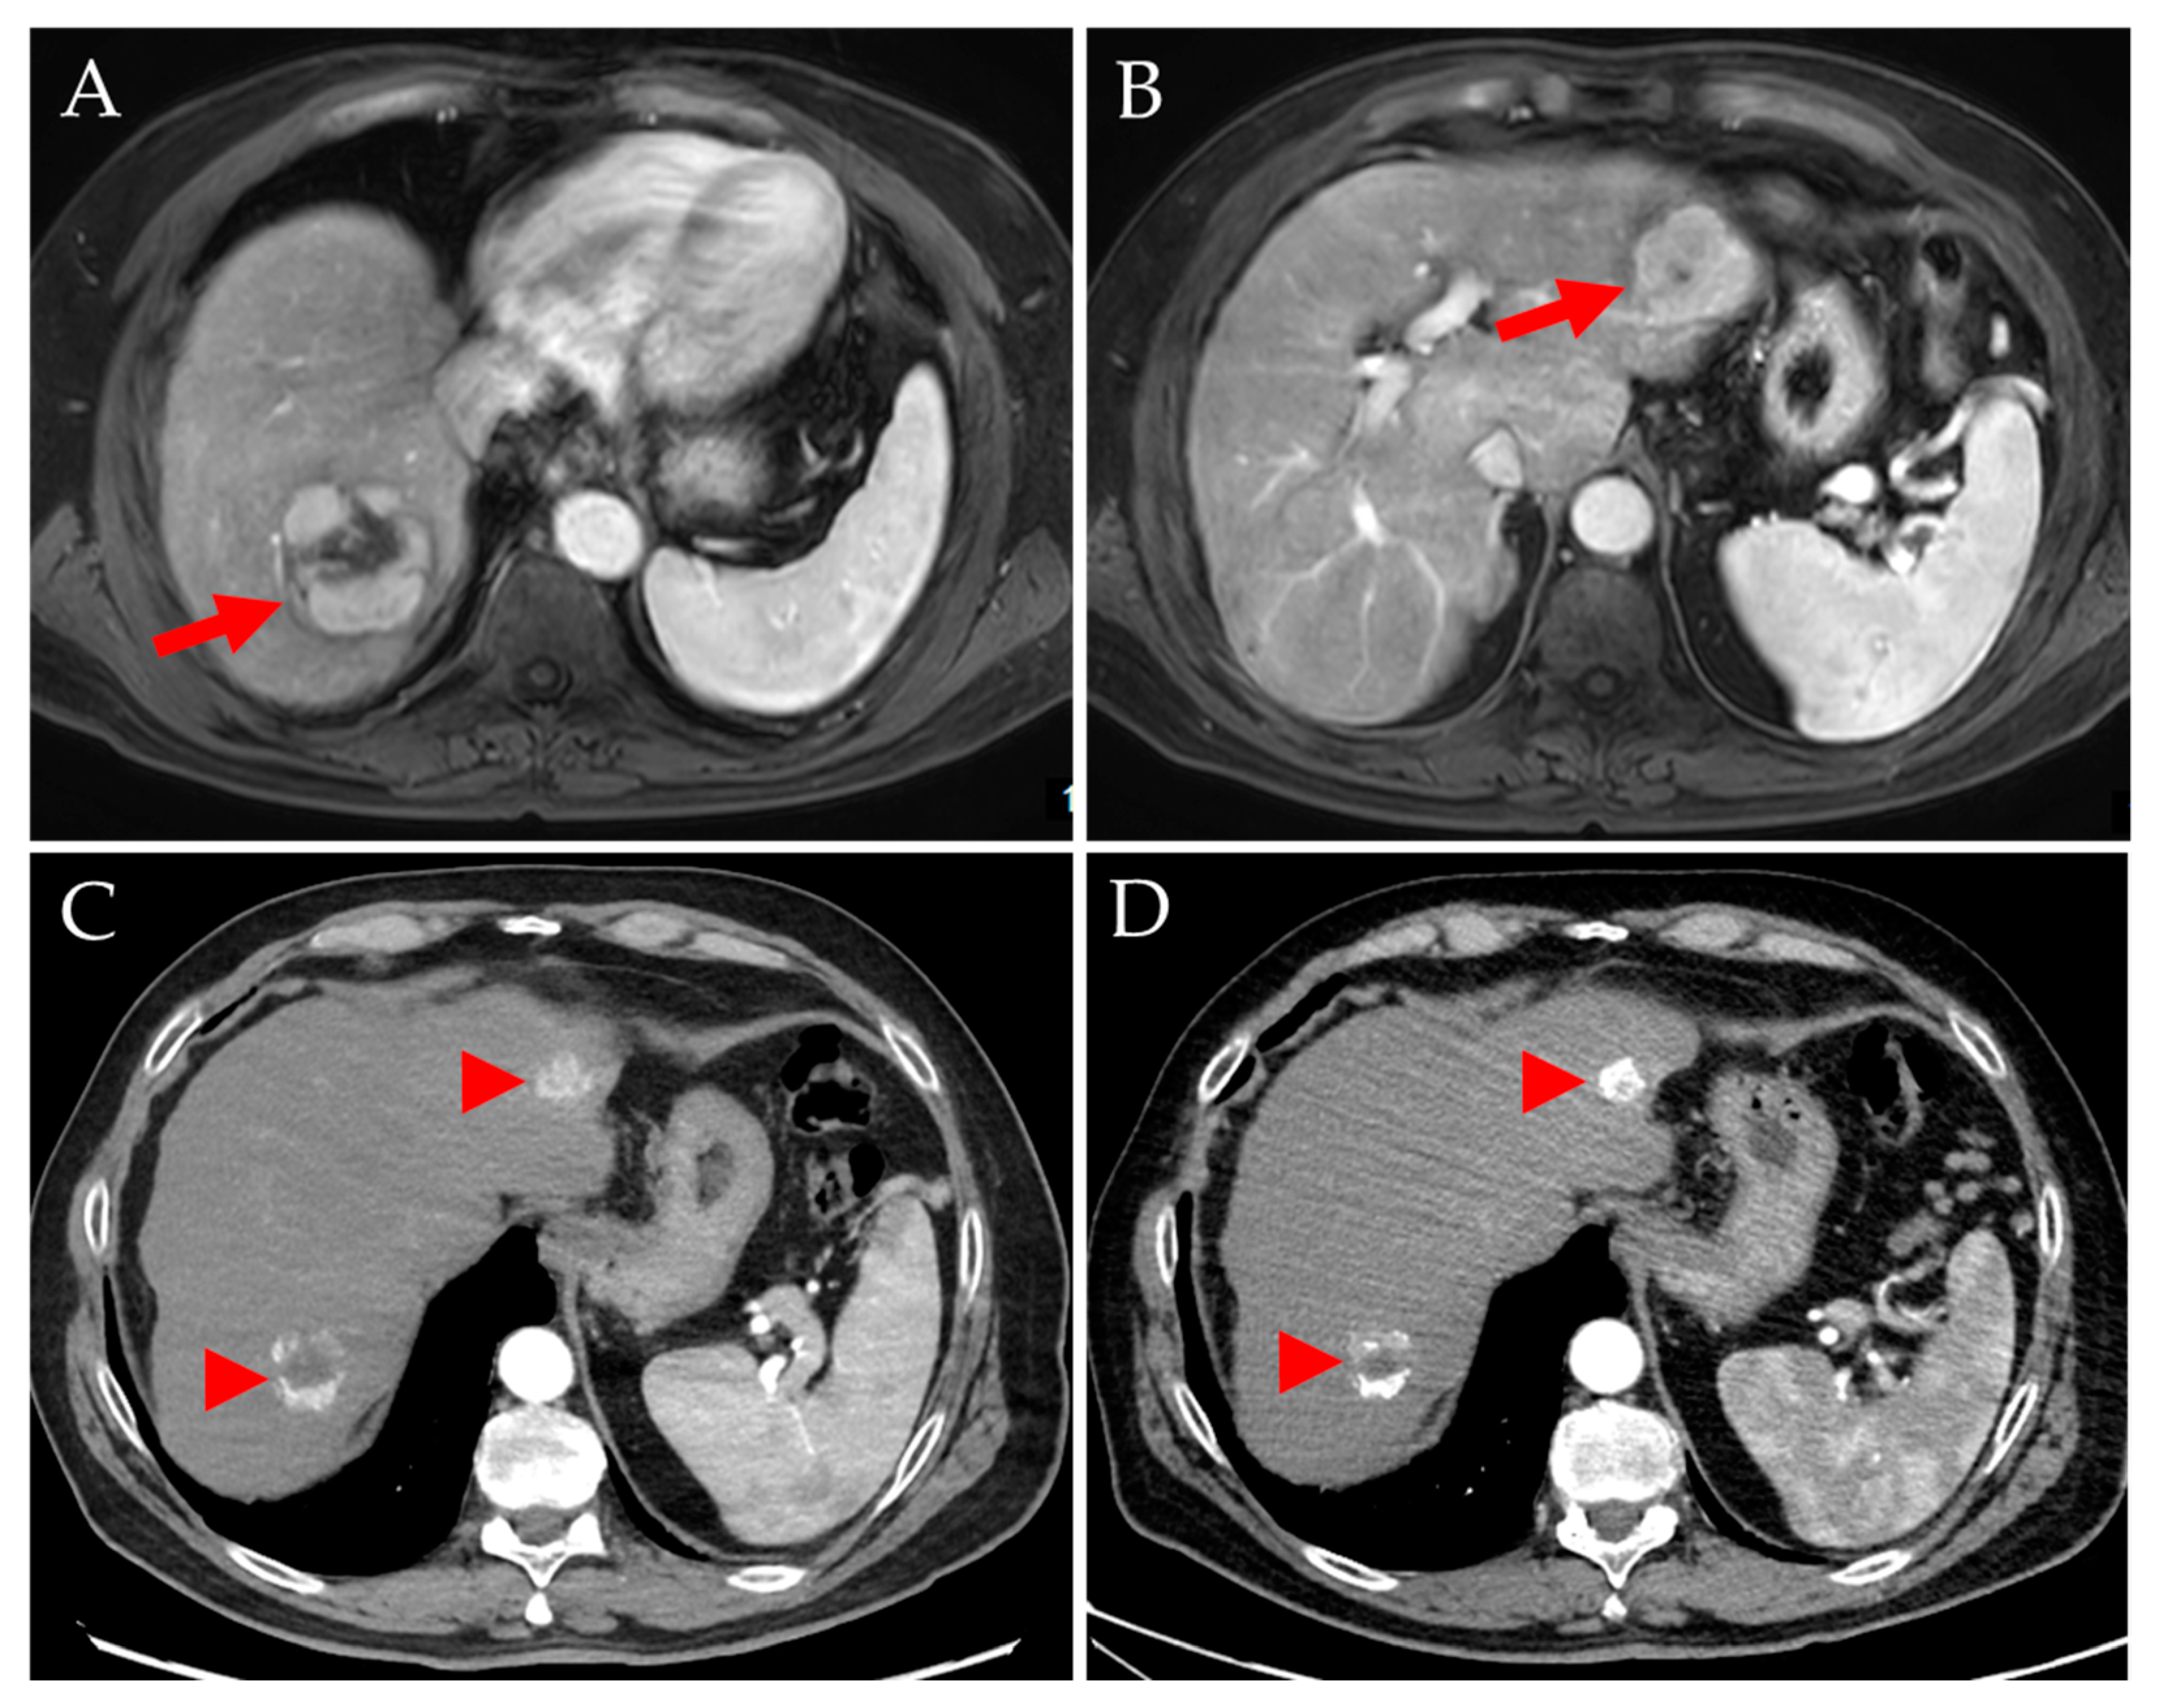

- A 58-year-old man with HCC stage II and severe liver cirrhosis (BCLC D, ALBI grade 3, Child–Pugh score C11, moderate ascites, bridging-to-transplant 166Ho-TARE of liver segment II, target 14% of whole liver, healthy target/tumor doses: 59 Gy/119 Gy). The patient was discharged as planned, but readmitted to hospital with acute or chronic liver failure (ACLF) grade 3, pneumonia, and sepsis. The Child–Pugh score deteriorated to C13. The patient died 6 days after 166Ho-TARE.

- A 74-year-old man with HCC stage II and liver cirrhosis (BCLC B, ALBI grade 2, Child–Pugh score A6, no ascites, palliative 166Ho-TARE of left liver lobe, 43% of whole liver, healthy target/tumor doses: 49 Gy/148 Gy). The follow-up at three months showed PR of the tumor, but moderate ascites (Child–Pugh score B8). The liver function deteriorated rapidly. The patient died 3.2 months after 166Ho-TARE.

- A 69-year-old man with HCC stage IIIB and liver cirrhosis (BCLC B, ALBI grade 2, Child–Pugh score B7, moderate ascites, palliative 166Ho-TARE of right liver lobe, target 55% of whole liver, healthy target/tumor doses: 41 Gy/114 Gy). The follow-up at three months showed PD in both liver lobes with macrovascular involvement and a Child–Pugh score of B8. The patient died 4.0 months after 166Ho-TARE.

- A 65-year-old man with HCC stage II in the liver segment IV, maximum diameter 19 cm compressing the portal vein and liver veins, no liver cirrhosis (BCLC C, ALBI grade 3, Child–Pugh score B8, no ascites, palliative 166Ho-TARE of the liver segment IV, 28% of whole liver, healthy target/tumor doses: 42 Gy/88 Gy; tumor not completely perfused). The follow-up at three months showed PR of the tumor and tumor progression in adjacent liver segments. Four months after 166Ho-TARE, the liver function deteriorated rapidly (Child–Pugh score C13). The patient died 5.6 months after 166Ho-TARE.